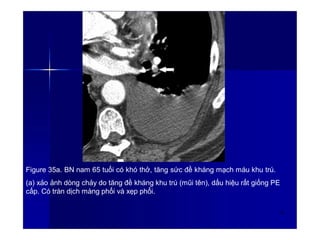

Figure 35a. BN nam 65 tuổi có khó thở, tăng sức đề kháng mạch máu khu trú.

(a) xảo ảnh dòng chảy do tăng đề kháng khu trú (mũi tên), dấu hiệu rất giống PE

cấp. Có tràn dịch màng phổi và xẹp phổi.

48